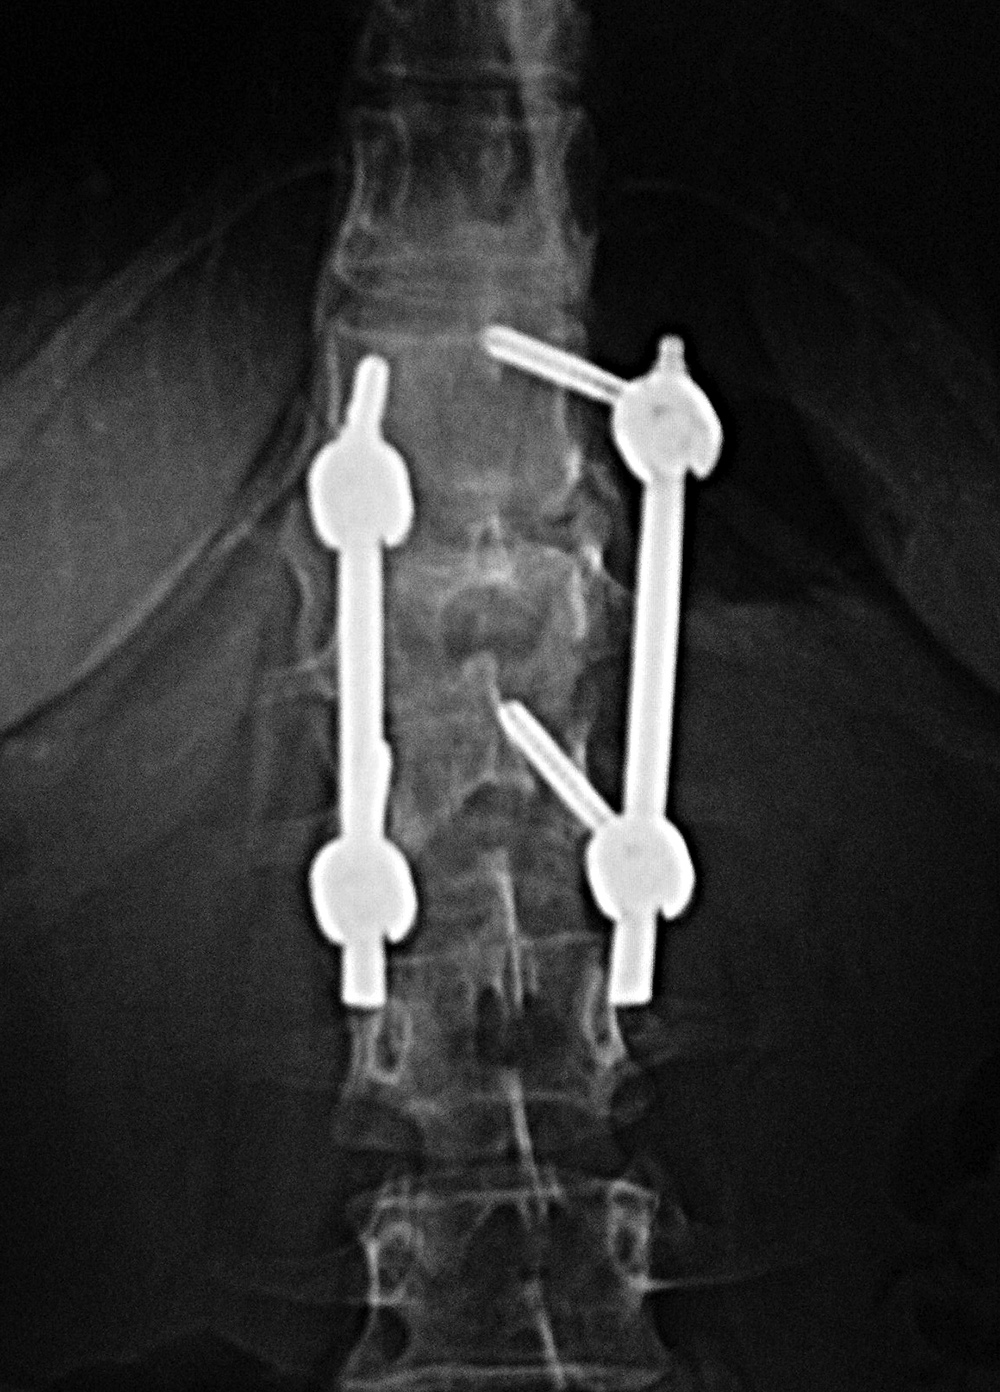

| Steffee Plates - Posterior Instrumented Lumbar Fusion (PLIF) |

| There is also a Brantigan disk cage at L5-S1 (arrow on lateral view) |

| Screws are placed through the pedicles into the vertebral bodies. The screws are connected together on each side with rods or a plate placed over the pedicle screws on each side. Some of these systems are also combined with posterolateral bony fusion masses. |